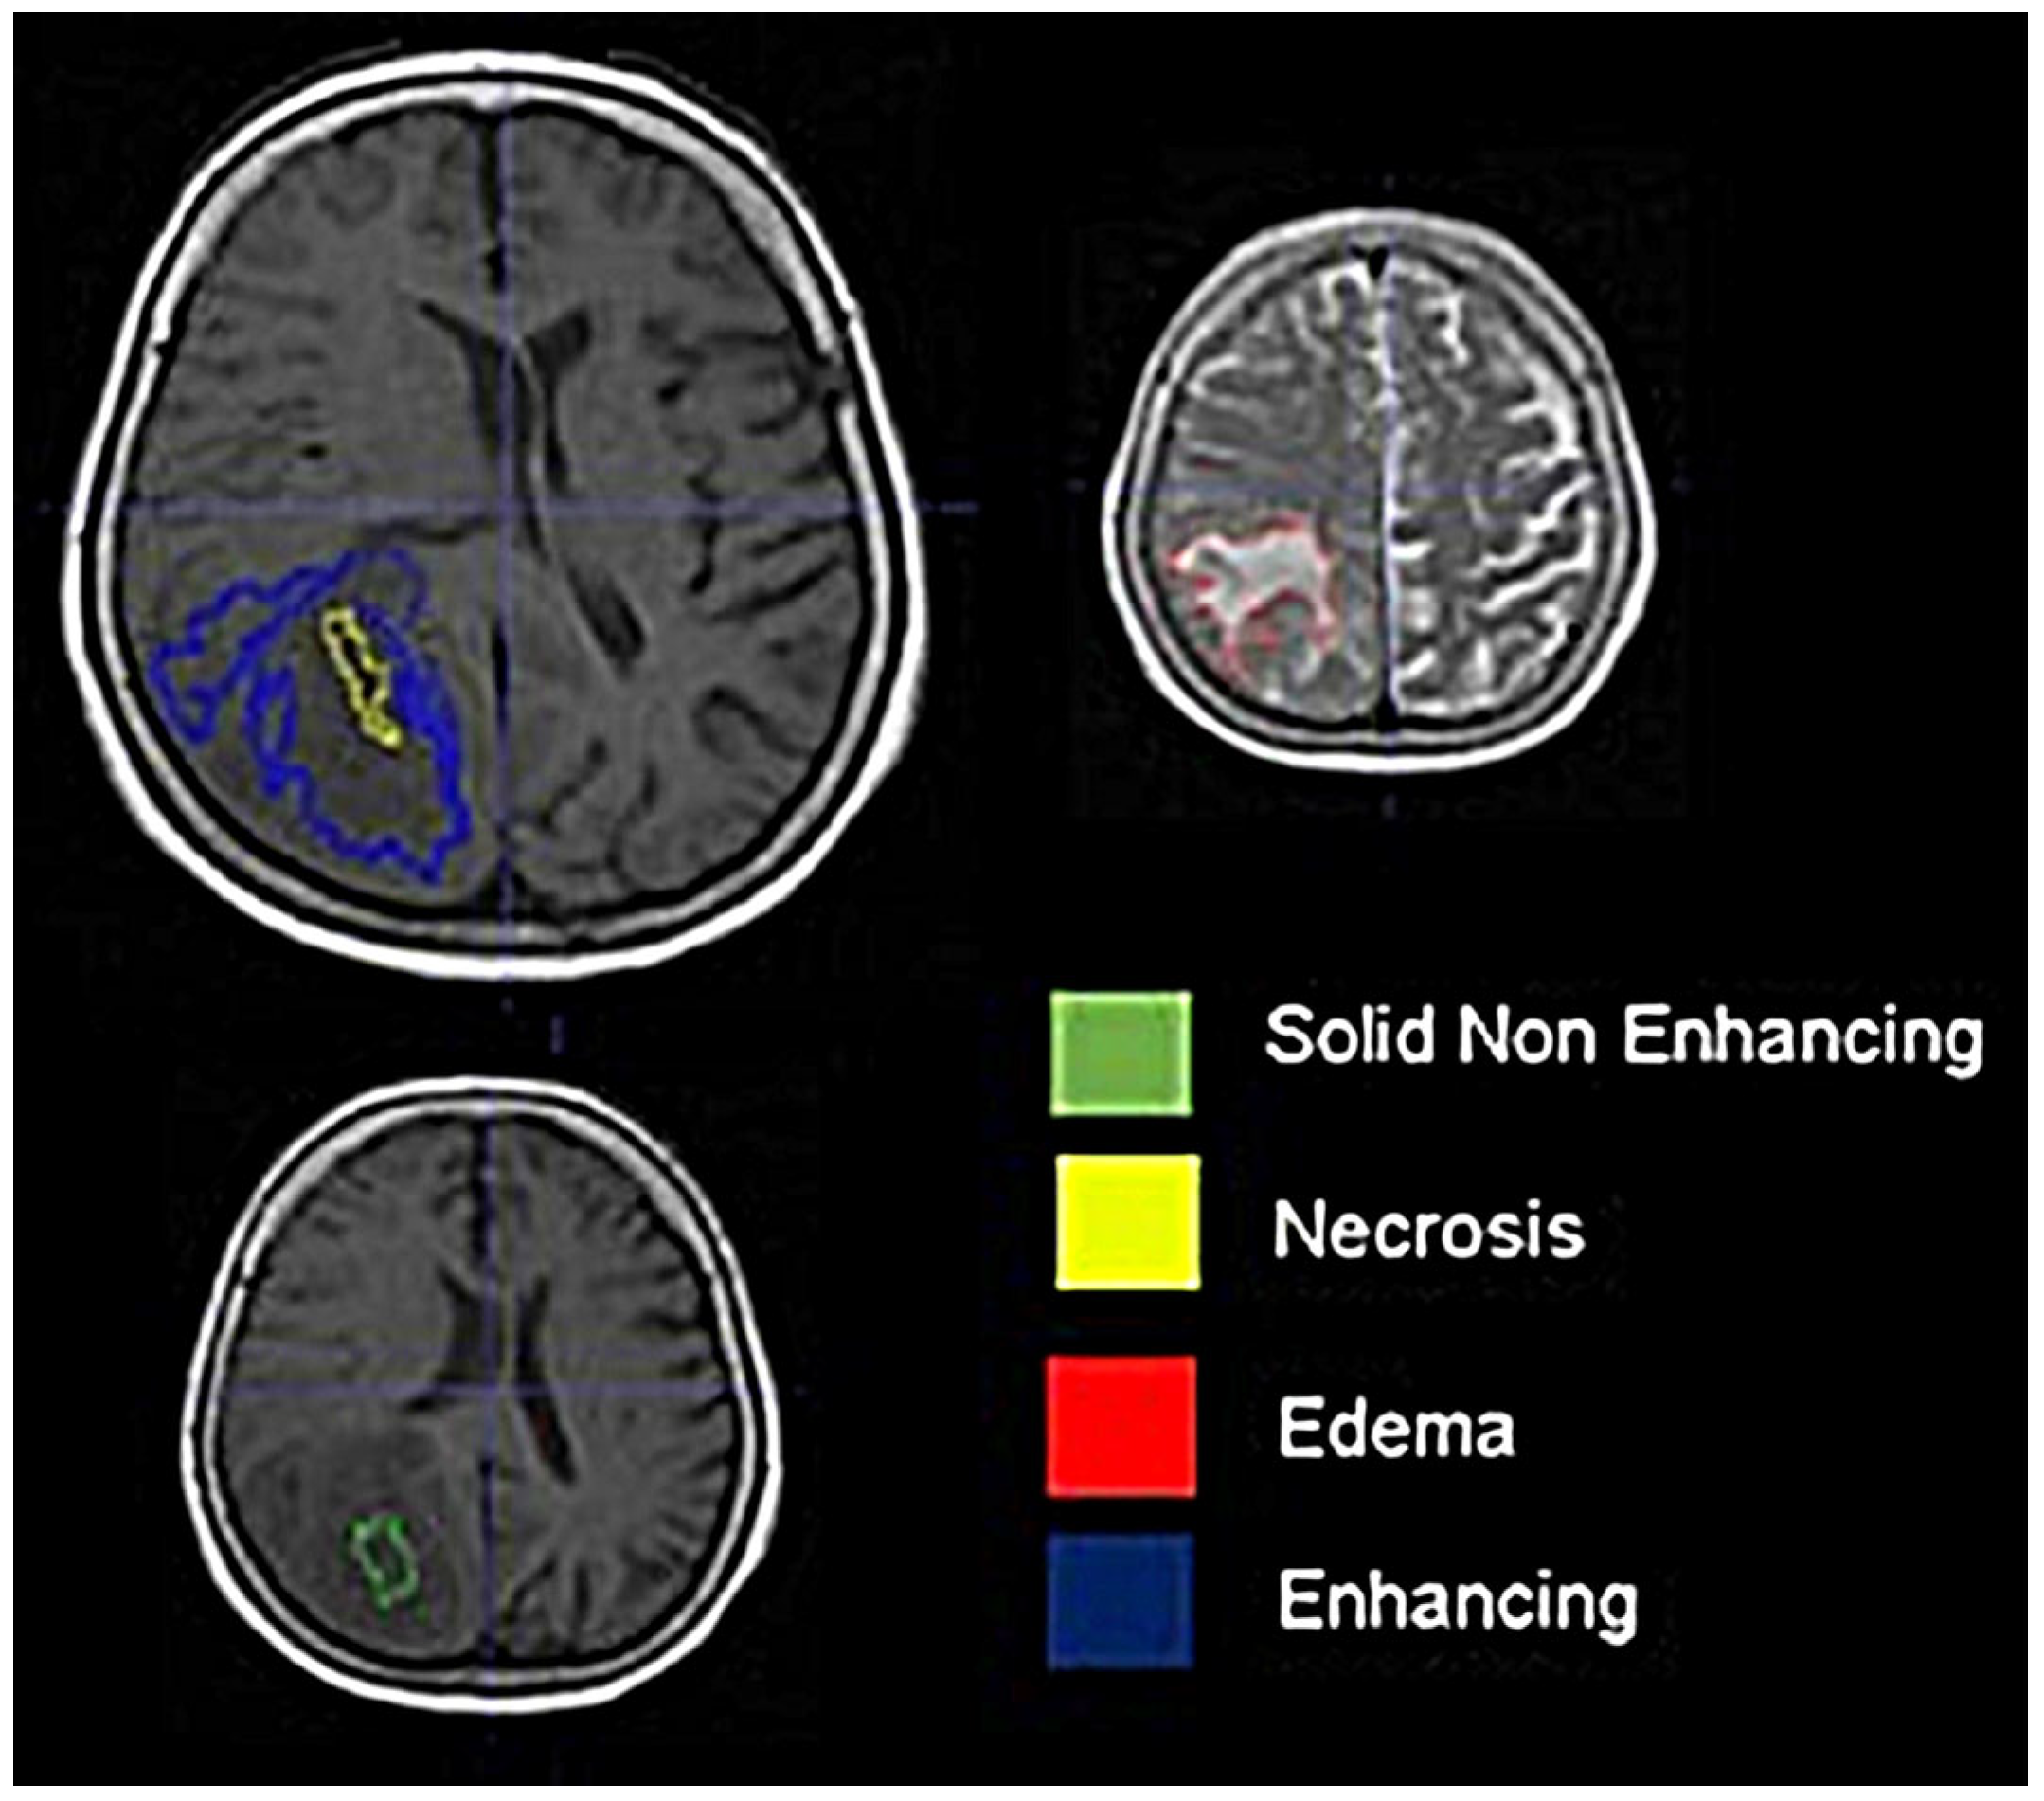

2.3. Image Processing